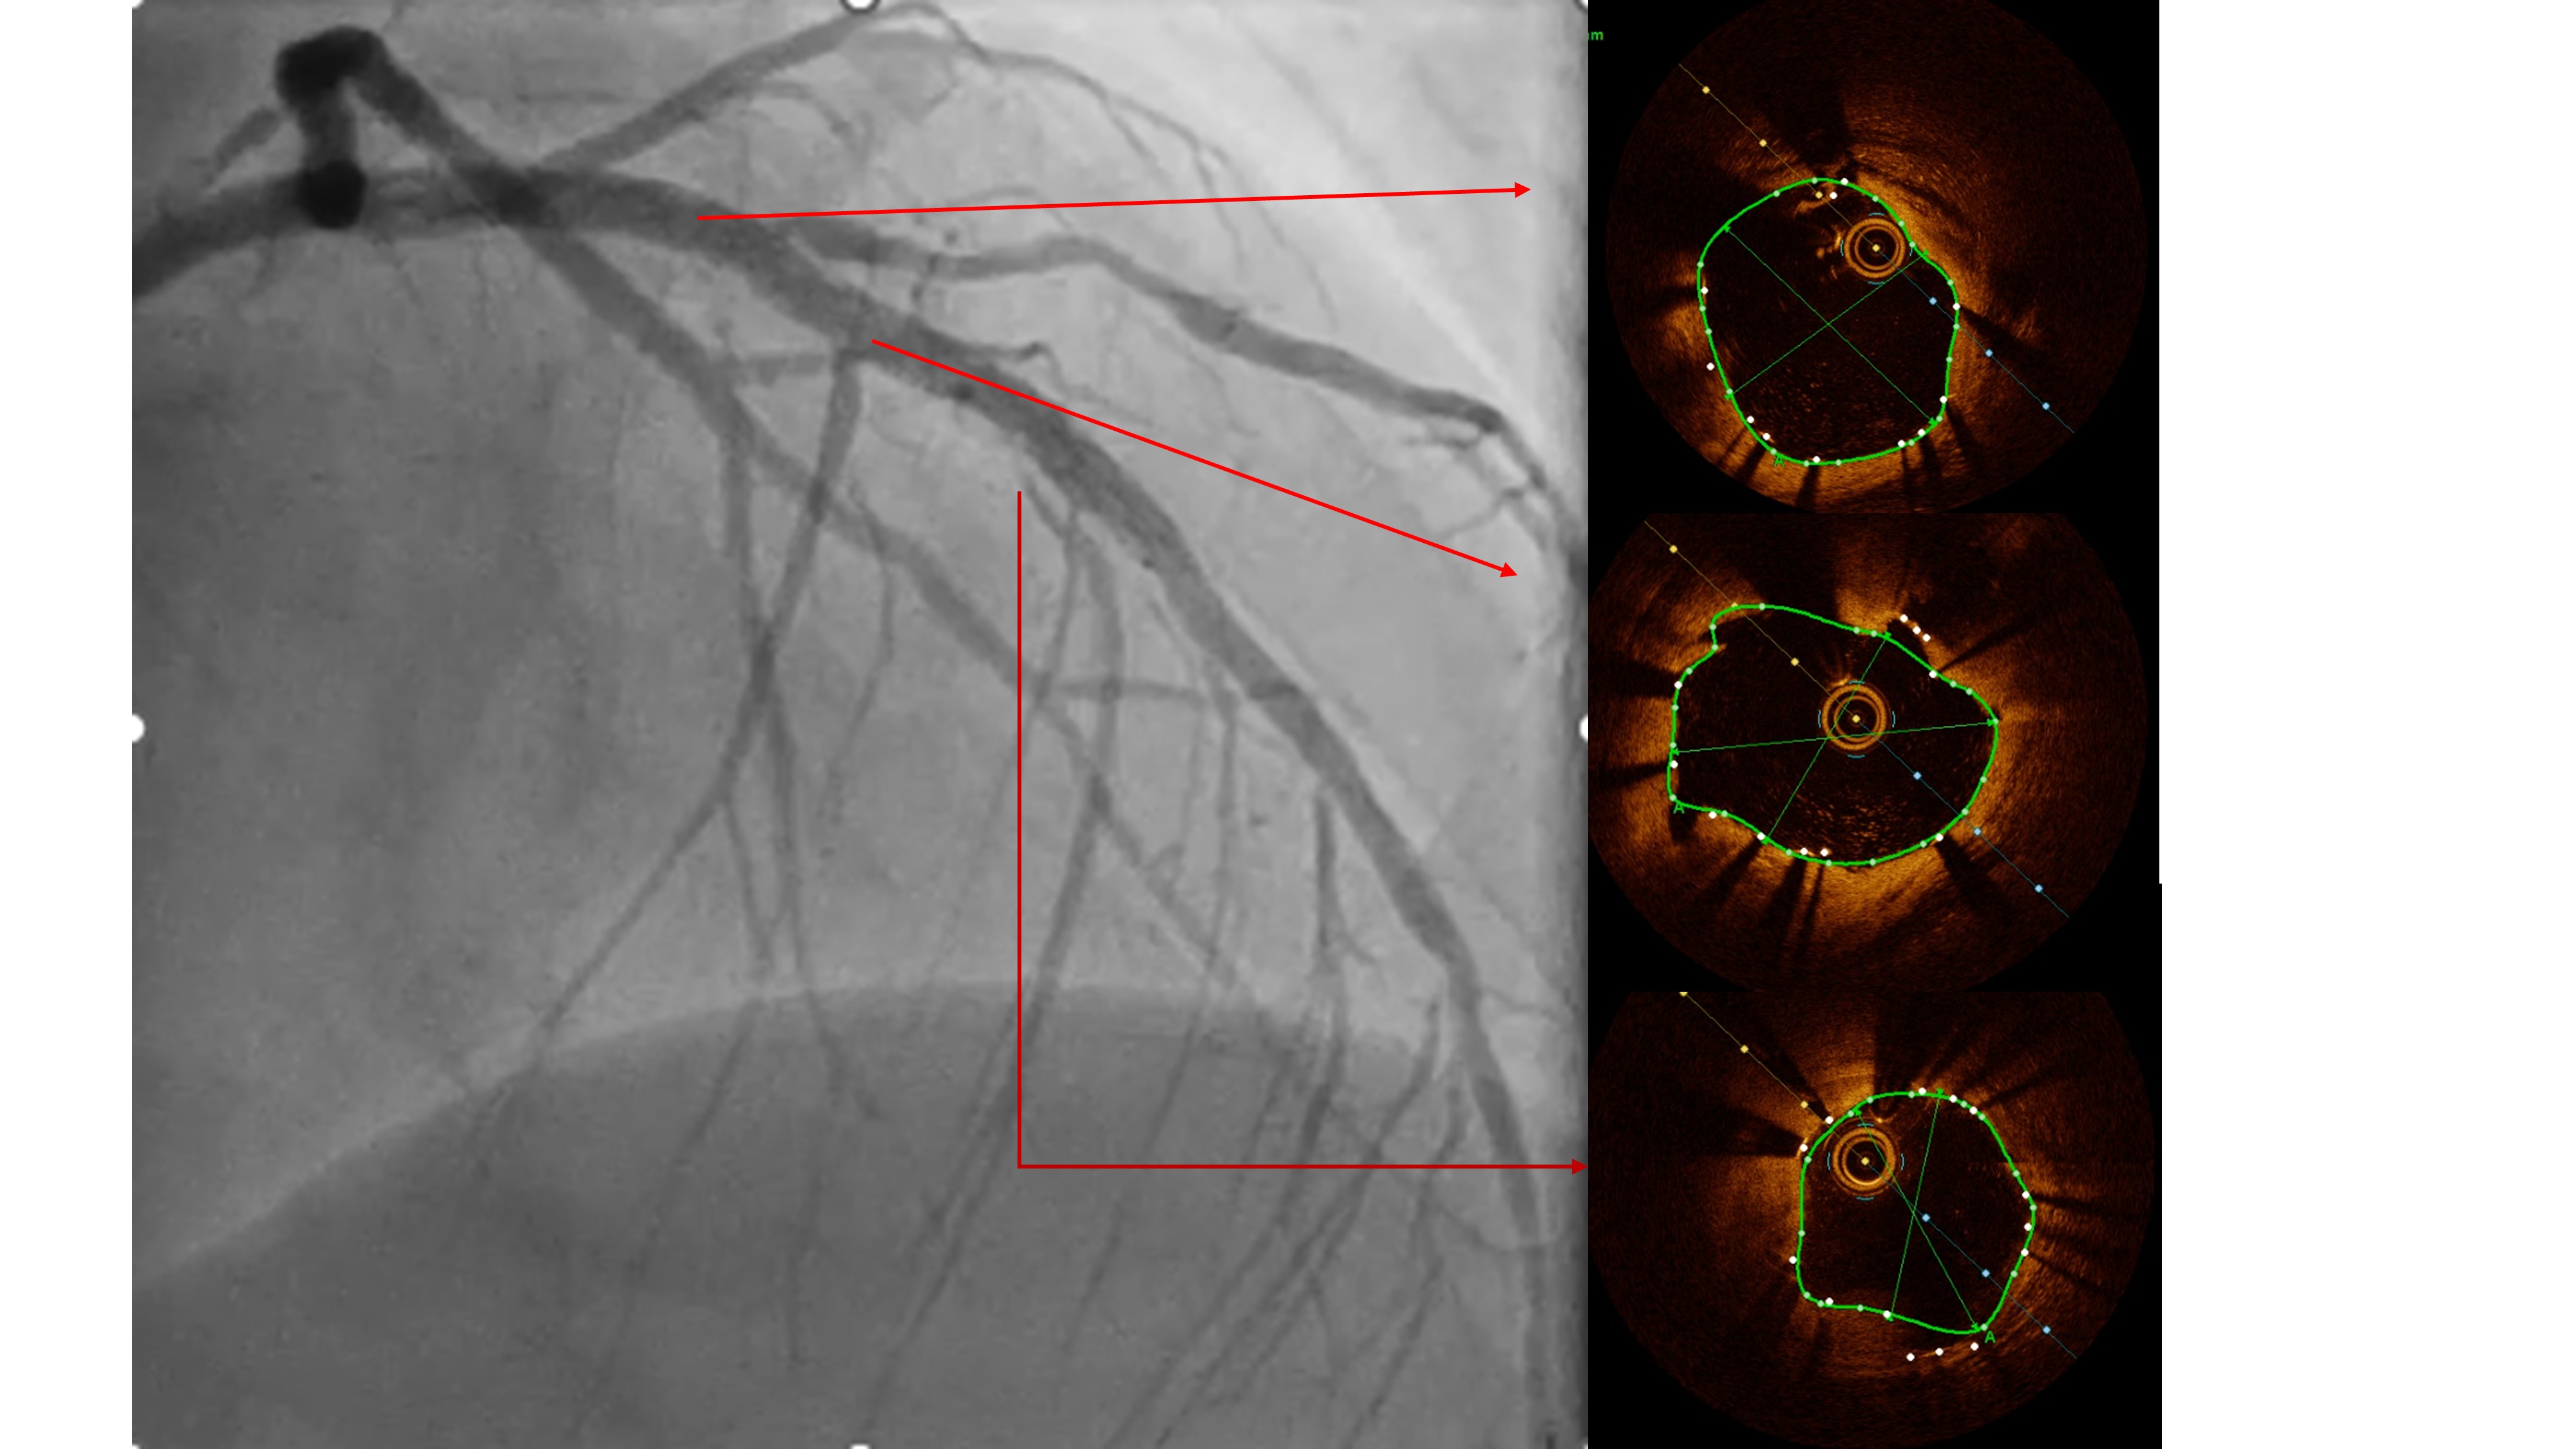

Two months ago, PCI of the LAD wasattempted. The guidewire successfully crossed to the distal LAD, but a 2.5 mmscoring balloon could not cross the mid lesion and showed a ¡°dog-bone¡±appearance upon inflation, so the procedure was stopped, and PCI of the LCx wasperformed instead. We reattempted PCI of the LAD using a Mach CLS 7 Fr guidingcatheter. A Fielder XT wire crossed to the distal LAD, but the OCT cathetercould not cross the lesion. Lesion preparation with a 2.0 mm scoring balloon athigh pressure and a 2.0 mm Wolverine cutting balloon enabled OCT passage. OCTimaging revealed fibrous and nodular calcification in the mid LAD, with aminimal lumen area of 1.71 mm and reference diameters of 4.0 mm (proximal) and3.3 mm (distal). Orbital atherectomy using a Diamondback 360 (1.25 mm crown)was performed carefully due to vessel tortuosity, with 10 runs at80,000–120,000 rpm. Post-atherectomy OCT showed reduced calcium burden andincreased lumen area. Further lesion preparation with 2.5 and 2.75 mm scoringballoons showed no ¡°dog-bone¡± sign, indicating adequate calcium fracture. A 3.0¡¿ 46 mm Amphilimus DES was implanted in the proximal–mid LAD and post-dilatedwith a 3.5 mm NC balloon. Final angiography showed TIMI 3 flow withoutdissection. Post-stent OCT showed good apposition, MSA 8.84 mm©÷ proximally and5.73 mm©÷ distally, with 99% expansion. The patient remained hemodynamicallystable and was discharged the following day.